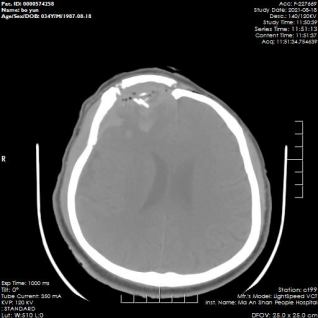

到達(dá)醫(yī)院急診科后,科室立即為卜師傅開通綠色通道,并請(qǐng)相關(guān)科室急會(huì)診。神經(jīng)外科急救團(tuán)隊(duì)打開患者的傷口后,還是倒吸了一口涼氣,整個(gè)左側(cè)眼眶部、額部一個(gè)巨大的“×”形爆裂傷口,腦組織、粉碎的顱骨骨片、頭發(fā)、污染異物隨著鮮血直往外流……一場(chǎng)生死時(shí)速的急救瞬間展開:抗休克、備血、簡(jiǎn)單處理傷口、緊急做CT、通知手術(shù)室,各項(xiàng)術(shù)前準(zhǔn)備工作有條不紊地進(jìn)行著。急診頭顱CT提示患者左側(cè)眼眶骨、額骨開放性骨折,粉碎的骨片嵌入腦內(nèi)伴血腫形成、腦組織開放、左側(cè)眼球移向腦內(nèi)、顱底多發(fā)性粉碎性骨折。

術(shù)前CT,可見顱內(nèi)血腫及游離碎骨片